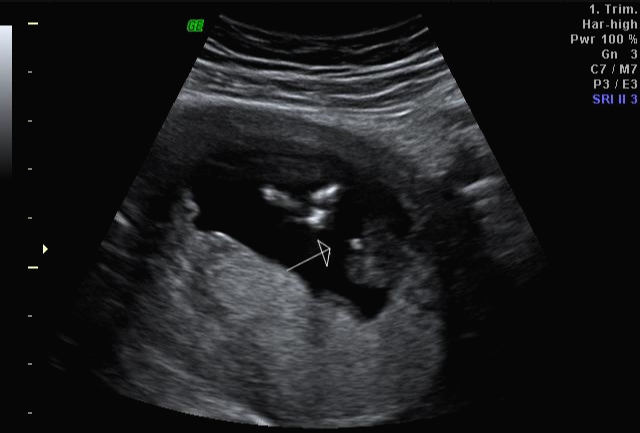

그리고 초음파 봐주시는 분께서 13주차가 되면 정확히 알 수 있으니 다음 주에 오라고 하셔서 일주일 뒤 다시 방문을 했습니다. (위에 사진은 12주 차 때 아들이라고 보여주신 초음파 사진이에요~ 화살표 보면 툭 튀어나와있는 부분을 보여주면서 아들이라고 하셨어요~)

아 진짜 전문가는 다르구나~ 이렇게 이른 주수에도 성별을 알 수가 있구나 생각을 했지만 이 시기 때는 성별을 정확히 알 수 없다는 글들을 봐서 살짝~ 의심스럽기도 했지만 그래도 100프로라니깐 ㅎㅎ 믿어보았어요~ 근데 위에 사진을 보면 성별을 알 수 있는 각도 법이 있는데 각도가 딸 같아서 긴가민가~하긴 했지만 의심은 잠시! 전문가 분을 믿기로 ㅋㅋㅋㅋ